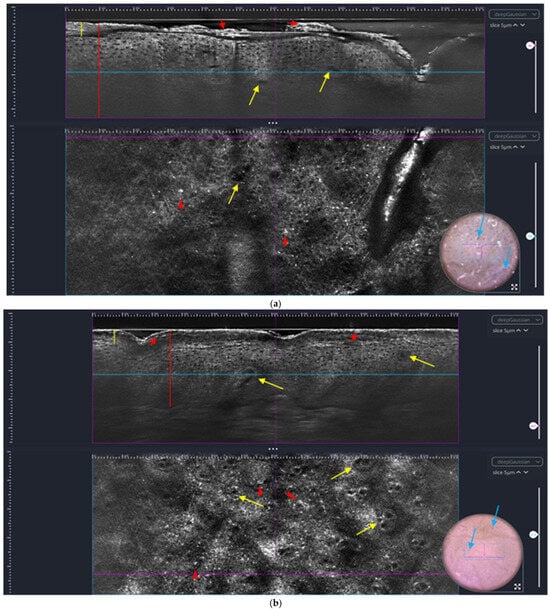

A study plaque (SP) and control area (CoA) were chosen before the initiation of therapy. The SP’s localization was not restricted; the CoA had to be clinically healthy skin and, if possible, located in a body region similar to that of the SP. Therapeutic response in the SP was evaluated by changes as observed by LC-OCT and, clinically, by determining the LPSI. The LPSI was designed in accordance with the LPSI already established by Errichetti [27] as a five-point scale (scaling (0–4), erythema (0–4), and infiltration (0–4)), ranging from 0 to the highest score of 12. The overall therapeutic response was assessed using the PASI score and DLQI. The probability of psoriatic arthritis was screened for with the German psoriasis arthritis diagnostic questionnaire (GEPARD). Patients underwent the first screening before starting the new treatment (V0), as well as 4 weeks (V1) and 12 weeks (V2) after the initiation of therapy. Use of topical corticosteroids on the SP was omitted during this period in accordance with the patients. The LC-OCT scanning of the SP and CoA, dermoscopy, clinical photography, and the assessment of the LPSI, PASI, DLQI, and GEPARD were conducted at all study visits by our investigator team. For one patient, the DLQI and GEPARD were missing for V2. LC-OCT scanning was performed by capturing a 3D stack at three different areas in the SP and CoA after the application of paraffin oil. The best scan of each lesion and time point was chosen for analysis, including a manual measurement of hyperkeratosis/stratum corneum (SC) and ET (see Figure 1a–c). If the dermo-epidermal junction (DEJ) could not be detected by LC-OCT because of excessive acanthosis or hyperkeratosis, the highest measurable value was used for statistical analysis (Figure 1a).

Figure 1.

(a) V0 SP right elbow: vertical (top) and horizontal (bottom). Line-field confocal optical coherence tomography picture (horizontal image size: 1.2 mm × 0.5 mm; vertical image size: 1.2 mm × 0.4 mm) of SP before start of therapy (LPSI 7) with hyperkeratosis (yellow line), parakeratosis (red arrows), dilated vessels (yellow arrows) in elongated rete ridges, acanthosis (red line), and bright inflammatory cells in the epidermis (red arrowheads); accompanying dermatoscopic picture (bottom right corner, image size: 1.2 mm × 0.5 mm) with scales and dotted vessels (blue arrows). Abbreviations: V0 = visit 0 before start of treatment, SP = study plaque, LPSI = local psoriasis severity index. (b) V1 SP: right elbow: vertical (top) and horizontal (bottom). Line-field confocal optical coherence tomography (horizontal image size: 1.2 mm × 0.5 mm; vertical image size: 1.2 mm × 0.4 mm) of SP after 4 weeks of therapy (LPSI 4), less hyperkeratosis (yellow line) and parakeratosis (red arrows), dilated vessels (yellow arrows) in elongated rete ridges, less acanthosis (red line), and bright inflammatory cells in the epidermis (red arrowheads); accompanying dermatoscopic picture (bottom right corner, image size: 1.2 mm × 0.5 mm) with no more scales and only very few dotted vessels (blue arrows). Abbreviations: V1 = visit 1 after 4 weeks of treatment, SP = study plaque, LPSI = local psoriasis severity index. (c) V2 SP: right elbow: vertical (top) and horizontal (bottom). Line-field confocal optical coherence tomography (horizontal image size: 1.2 mm × 0.5 mm; vertical image size: 1.2 mm × 0.4 mm) of SP after 12 weeks of therapy: clinically, skin almost completely cleared (LPSI of 1, only minimal erythema left), no more hyperkeratosis (yellow line indicating stratum corneum) or parakeratosis, dilated vessels (yellow arrows) without elongated rete ridges, no more acanthosis (red line), and a few bright inflammatory cells in the epidermis (red arrowheads) and pigmented keratinocytes around the dermal papillae (blue arrowheads); accompanying dermatoscopic picture (bottom right corner, image size: 1.2 mm × 0.5 mm) with no more scales and a few dotted vessels (blue arrows, purple pigment as skin marker particles in between). Abbreviations: V2 = visit 2 after 12 weeks of treatment, SP = study plaque, LPSI = local psoriasis severity index.